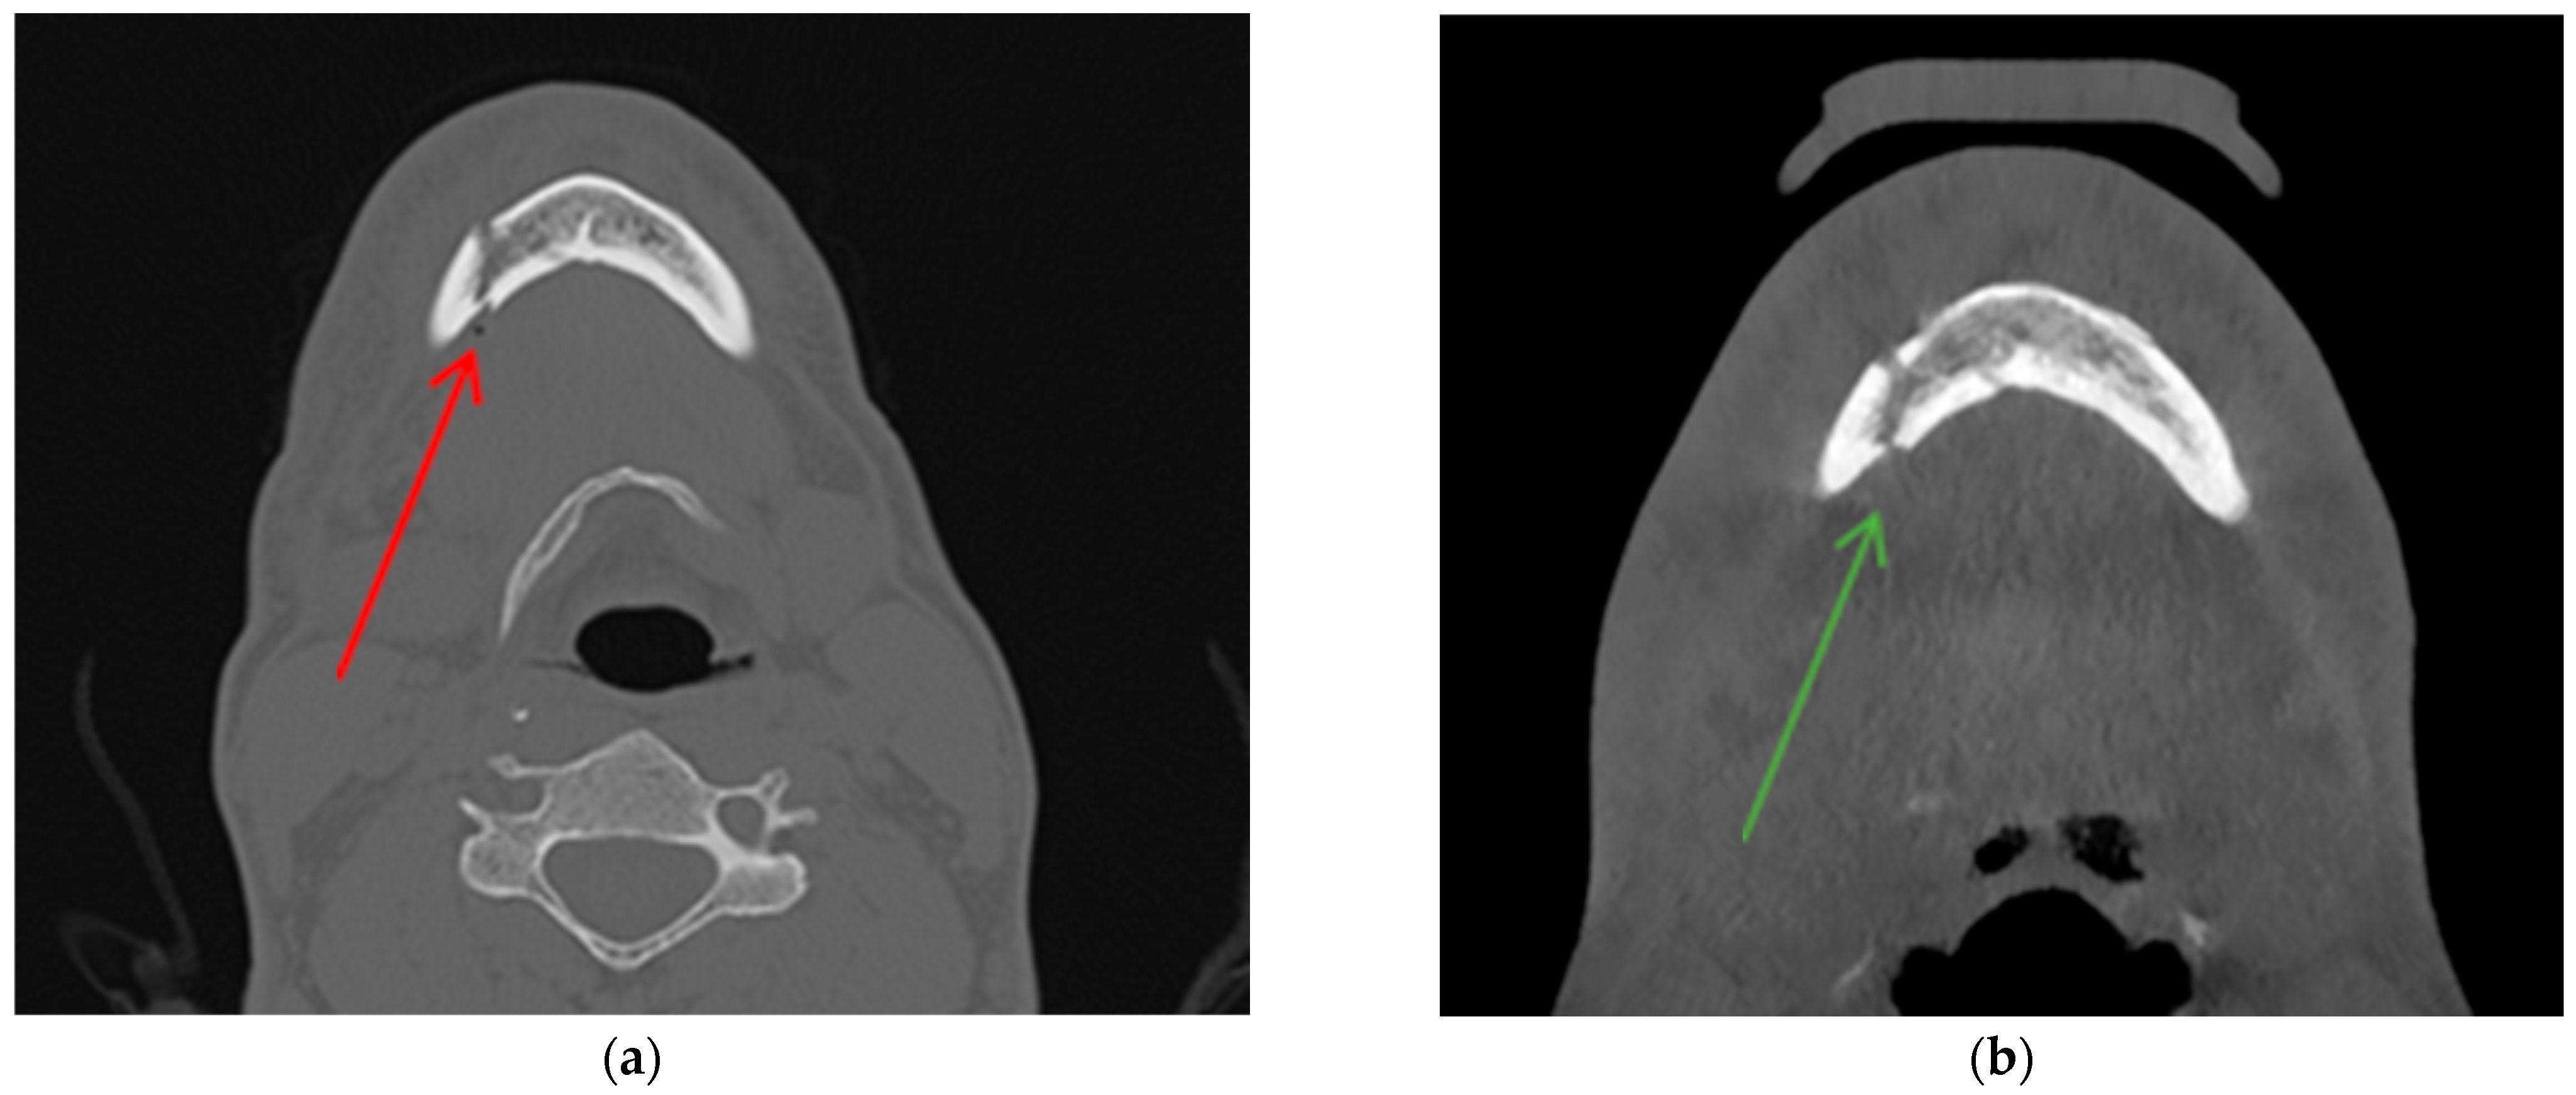

- True positive (TP)—diagnosed body/angle fracture + presence of AS in soft tissues.

- False positive (FP)—no body/angle fracture + presence of AS in soft tissues.

- True negative (TN)—no body/angle fracture + no AS in soft tissues.

- False negative (FN)—diagnosed body/angle fracture + no AS in soft tissues.